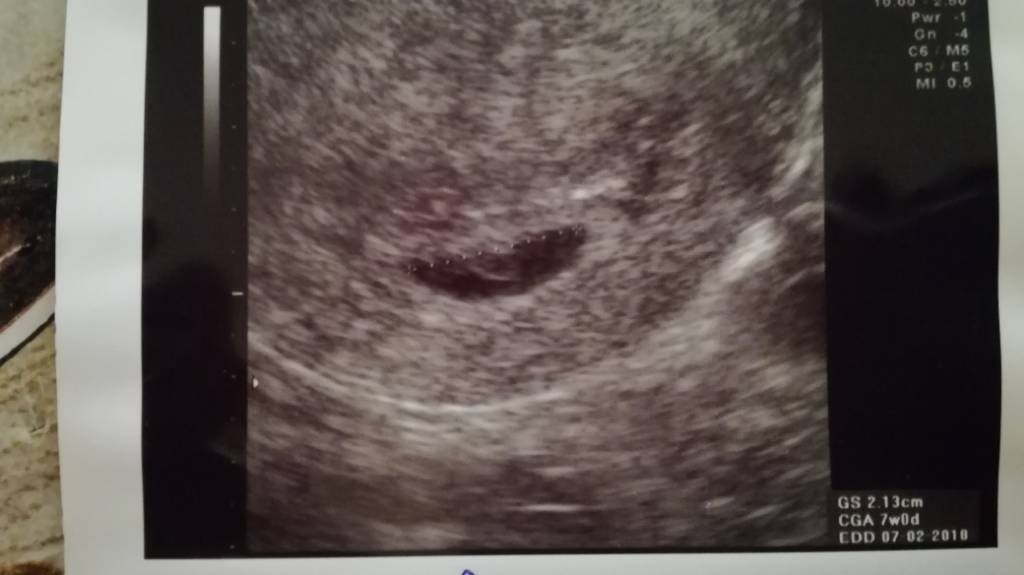

Dzisiaj byłam na wizycie, tak sie stresowalam ze zabralam męża ze sobą.....nareszcie zobaczyliśmy naszą fasolkę,ma 6,5mmserduszka jeszcze dokladnie nie bylo widać ale pulsowanie juz jest. Wszystko jest w porządku, mam zrobic wszystkie badania i za tydzien z wynikami bo kończy mi sie zwolnienie.

Termin na ok 13.02